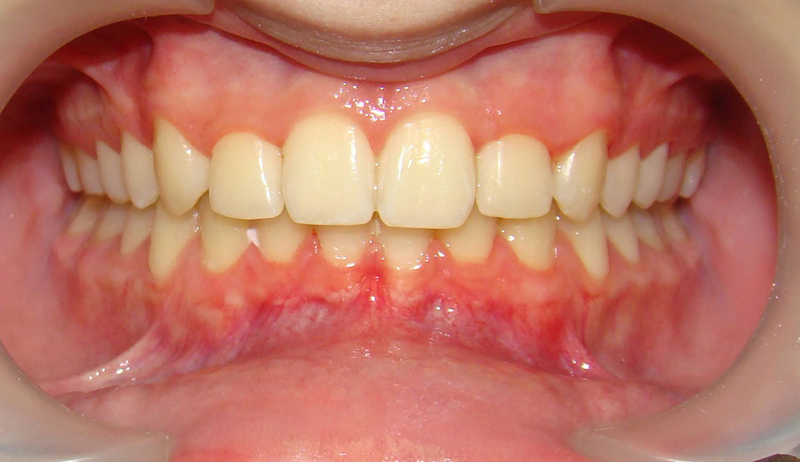

А это уже молодой человек 10 лет. Тоже получилось справиться без удаления. Хоть оно и было показано. Но мальчик очень упорно носил специальные аппаратики и резиночки. Покажу со всех сторон. Этот случай победил в конкурсе на конференции